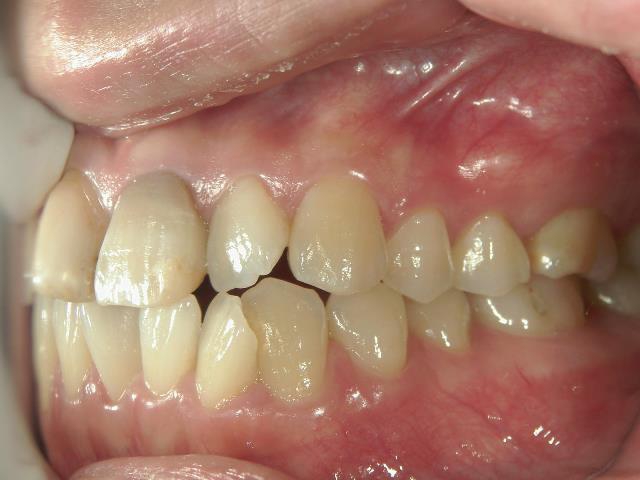

矯正歯科 治療前矯正歯科 治療前

矯正歯科 治療前 アクア/上顎1年4カ月→プチワイヤー矯正/上下顎2年

no.37_7548_治療前_右.JPGno.37_7548_治療前_正面.JPGno.37_7548_治療前_左.JPG